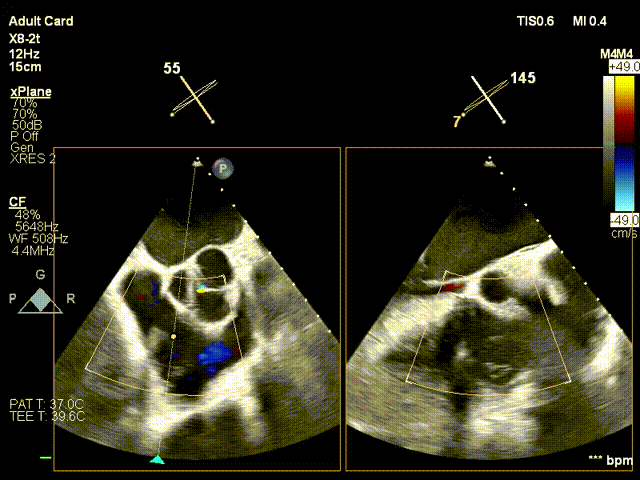

Following a comprehensive multi-dimensional evaluation by the cardiology team at Jiangsu Provincial People's Hospital, and in consideration of the patient's tricuspid valve lesion characteristics and anatomical structure, a precise surgical plan of dual-clip K-Clip® implantation was formulated to achieve optimal therapeutic outcomes. A 12T K-Clip® was implanted at the posterior tricuspid annulus, and a 14T K-Clip® was implanted at the anteroposterior commissure. Through precisely positioned dual-point implantation, this procedure effectively reduces the tricuspid annulus area and enhances leaflet coaptation, directly alleviating tricuspid regurgitation at the anatomical level and laying a critical foundation for the patient's postoperative recovery.

2. Steer and rotate the delivery system toward the target; advance and deploy the anchoring screw under 3D MPR plane guidance

3. After adjusting orientation, position the clamping arms for landing

4. The same procedure is performed for the second clip; the clip morphology is stable under ultrasound